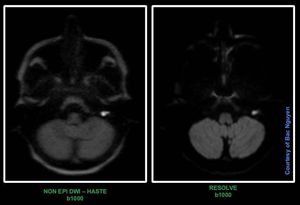

Cholesteatoma – RESOLVE vs non EPI HASTE DWI @ Siemens 1.5T Aera Can RESOLVE technique replace non EPI HASTE DWI for cases like cholesteatoma? A very good paper highlighting this question. Absolutely worth reading. https://www.ncbi.nlm.nih.gov/pmc/articles/PMC5441457/pdf/WJR-9-217.pdf#s_mri #siemens #mri #cholesteatoma